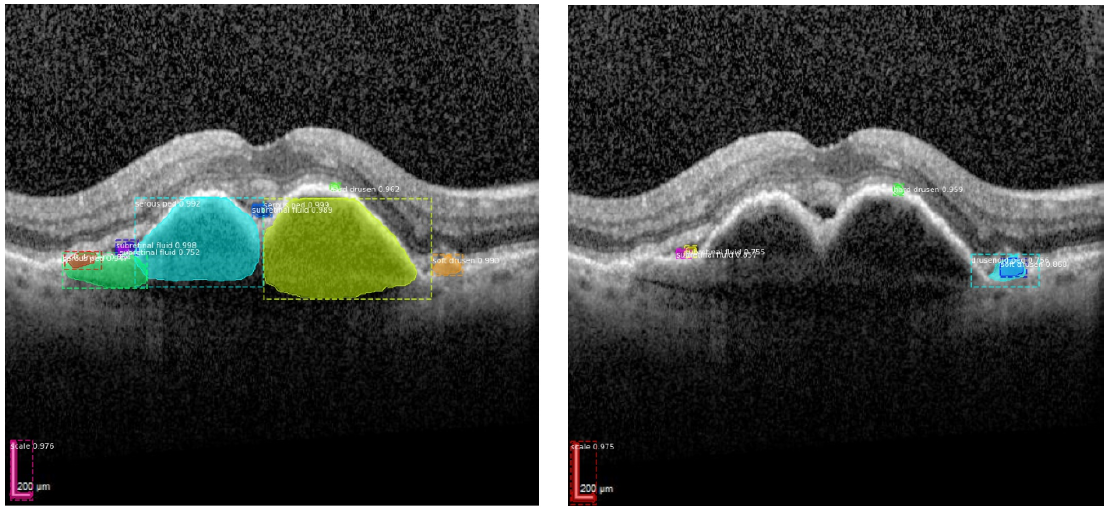

In collaboration with Prof. Malcherek from the Department of Computer Science at the University of Applied Sciences in Darmstadt, Germany, we have developed deep learning algorithms that can accurately distinguish between active and inactive neovascular AMD. In another project, a deep learning algorithm was trained to automatically detect various changes typical of AMD in OCT images. Another focus is the automatic detection of glaucomatous optic nerve changes in glaucoma patients. An algorithm trained on fundus photographs achieved good statistical power in discriminating between optic nerves with glaucomatous damage and those with conspicuous changes but no nerve fiber layer loss. In this case, the algorithm performed as well as a glaucoma specialist when additional metadata were included. Further projects to establish methods for image annotation are in preparation.